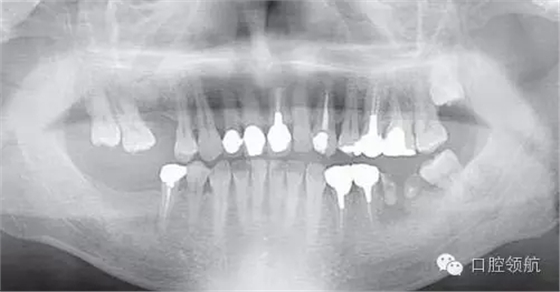

患者,38歲,男性,作為需要全面治療的患者來院?;局委熀?,右下頜磨牙區(qū)及右上頜磨牙區(qū),還有拔牙后的左下頜磨牙缺損區(qū),擬進行種植修復。圖1為初診時的曲面斷層影像,問診,模型診斷,曲面斷層檢查均未見異常,因此,最先在右下頜磨牙缺損區(qū),繼而在右上頜磨牙缺損區(qū)植入種植體,這些種植體愈合良好。

圖1 初診時的曲面斷層影像。